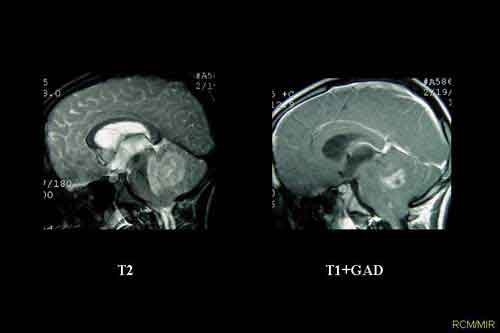

“Abbiamo quindi inattivato Tis21 in una linea di topi che sviluppa il medulloblastoma spontaneamente, ma con frequenza molto bassa, per generare una linea in cui la neoplasia si manifestasse nella gran parte della prole. Analizzando il cervelletto, dove abbiamo trovato un rilevante numero di lesioni neoplastiche di grosse dimensioni, abbiamo scoperto che i precursori delle cellule neuronali avevano perduto la capacità di muoversi dalla superficie di questa parte del cervello. In un topo normale infatti queste cellule, durante le prime fasi dello sviluppo postnatale, migrano dalla superficie verso l’interno, dove smettono di proliferare e differenziano in neuroni ‘maturi’. Se la migrazione è inibita, i precursori neuronali rimangono invece sulla superficie, dove continuano a proliferare andando incontro alla trasformazione neoplastica”.